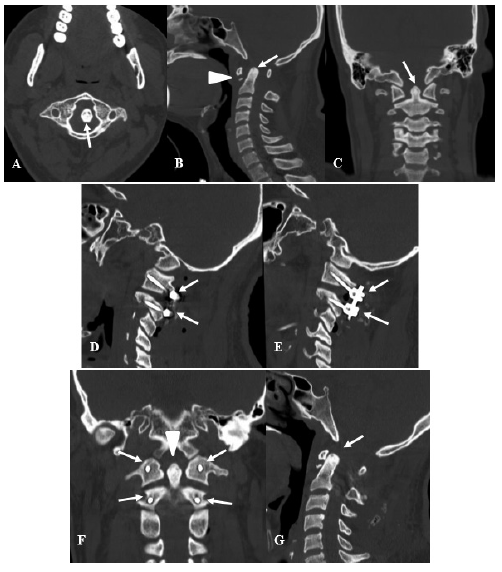

Se consideraron 31 pacientes, con una edad media de 51.16 años con un intervalo de confianza al 95% de 44.9 a 58.1 años, de los cuales 13 fueron mujeres (41.94%) y 18 fueron varones (58.06%). Sobre los antecedentes médicos, lo más frecuente fue la hipertensión arterial en el 29.03% de pacientes, seguido de la osteoporosis en el 25.81% (Tabla N° 1). Luego se procedió al análisis por grupo. Se muestra dos casos representativos de la presente serie en la Imagen N° 1 y N° 2.

En el grupo inflamatoria reumática se obtuvo 7 pacientes, que tenía una edad promedio de 59.29 años, con antecedente de artritis reumatoidea en todos los pacientes, además de tener el antecedente de osteoporosis en 6 pacientes (85.71%) y de hipertensión arterial en 4 pacientes (57.14%). El EVA preoperatorio promedio fue de 7.71, mientras que el EVA posoperatorio promedio fue de 2.29, con diferencia estadísticamente significativa (p menor de 0.001). El Nurick preoperatorio más frecuente fue 2 en 3 pacientes (42.84%), mientras que el Nurick posoperatorio más frecuente fue 1 en 3 pacientes (42.84%), lo cual no tuvo diferencia estadísticamente significativa (p=0.14). El déficit motor preoperatorio se presentó en 5 pacientes (71.43%), recuperando todos los pacientes, teniendo una recuperación leve en 3 pacientes (60%) y recuperación moderada en 2 pacientes (40%). Se presentó déficit sensitivo en 6 pacientes (85.71%), con recuperación en todos ellos. Sobre las imágenes preoperatorias, no se pudo determinar el DOA y DOP en 3 pacientes, y en el resto de pacientes se logró identificar subluxación anterior en 2 pacientes (28.57%) y subluxación posterior en 3 pacientes (42.86%), de los cuales 1 paciente tenía concomitantemente ambos subtipos de subluxación. La cirugía que se realizó fue la fijación cervical alta en 4 pacientes (57.14%) y la fijación occipitocervical en 3 pacientes (42.86%).Sólo hubo complicación en 1 paciente (14.29%) que fue una infección local. Hubo 1 falla del sistema, que requirió convertir una fijación cervical alta en fijación occipitocervical, logrando al final adecuada fusión en los 7 pacientes (100%) (Tabla N° 2 y 3).

el panorama clínico de estos pacientes, teniendo menos pacientes con inestabilidad atlantoaxial aislada, y un aumento de inestabilidad craneocervical compleja o inestabilidad subaxial. La inestabilidad cervical compleja requiere una fusión larga desde C0 hasta la columna torácica superior [4, 13, 14]. Esto lo hemos visto en nuestro estudio donde tuvimos 4 pacientes con fijación cervical alta y 3 pacientes que fueron complejos que tuvieron fijación occipitocervical inclusive hasta C4.